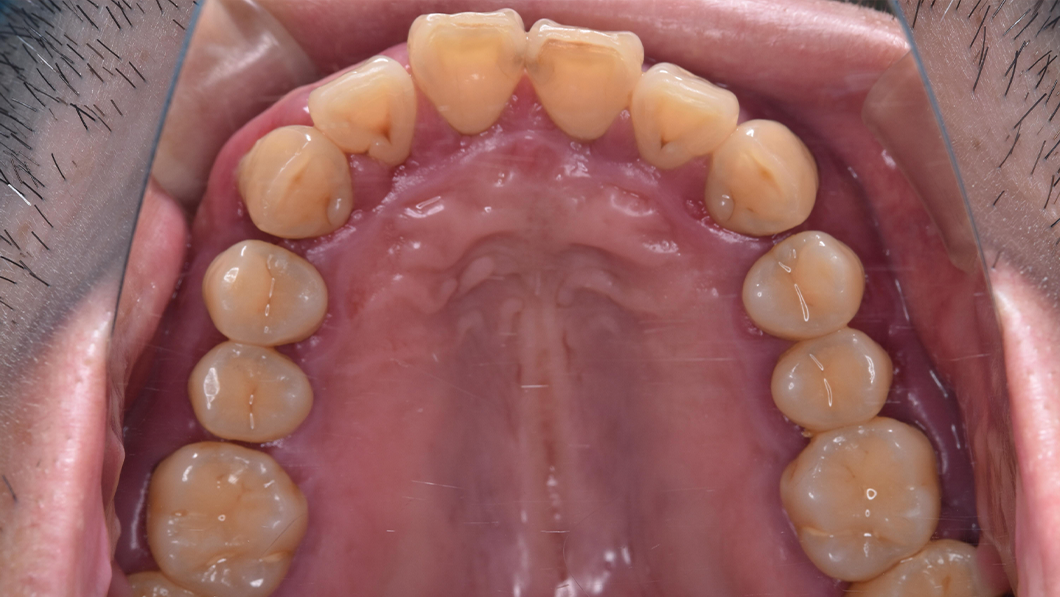

【40代 男性】歯周基本治療

治療後

主訴 全額的歯周病による歯周組織の炎症

治療内容 SC、SRP、歯科衛生士実地指導、TCH指導